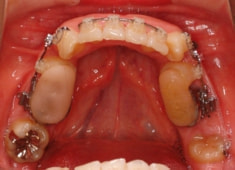

治療開始時